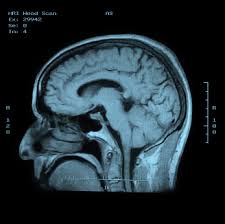

Chụp CT Scan, X-quang hoặc cộng hưởng từ động mạch.

Click vào ảnh để xem 4 hình ảnh minh họa